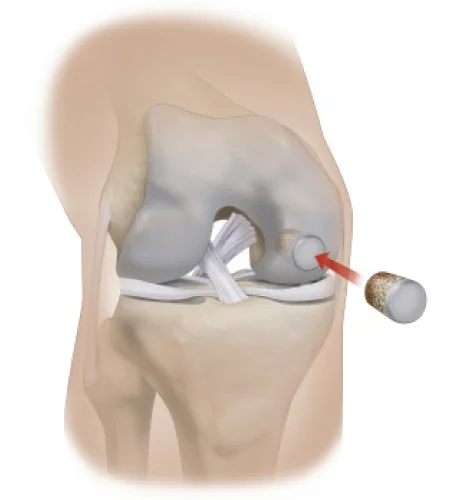

Chondral Defect

Treatment for cartilage damage in the knee, promoting healing and improving joint function.